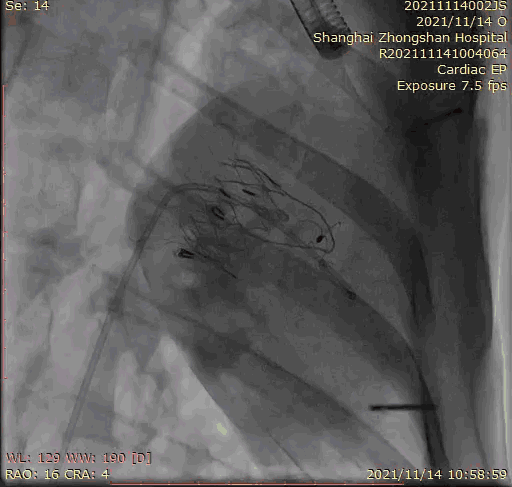

2021年11月14日星期日,復(fù)旦大學(xué)附屬中山醫(yī)院(以下簡稱中山醫(yī)院)葛均波院士團(tuán)隊成功應(yīng)用經(jīng)血管介入三尖瓣置換產(chǎn)品Lux-Valve Plus完成臨床前研究,并獲得圓滿成功!此次研究的成功預(yù)示經(jīng)血管三尖瓣產(chǎn)品Lux-Valve Plus已完成臨床前準(zhǔn)備,即將開啟后期的正式臨床研究!

上海中山醫(yī)院葛均波院士、錢菊英院長、周達(dá)新教授、潘文志教授、潘翠珍教授、李偉教授共同完成此次臨床前研究。術(shù)后葛均波院士對Lux-Valve Plus的器械操作性能給予了高度評價,DSA和超聲影像也顯示出在本次研究中Lux-Valve Plus的安全性和有效性俱佳。

本次臨床前研究經(jīng)右側(cè)頸靜脈置入LuX-Valve Plus輸送系統(tǒng)可調(diào)彎鞘管,在DSA及超聲引導(dǎo)下將人工三尖瓣瓣膜植入到原有三尖瓣位置,利用獨特的錨定技術(shù)將人工瓣膜支架可靠固定在預(yù)定的位置。